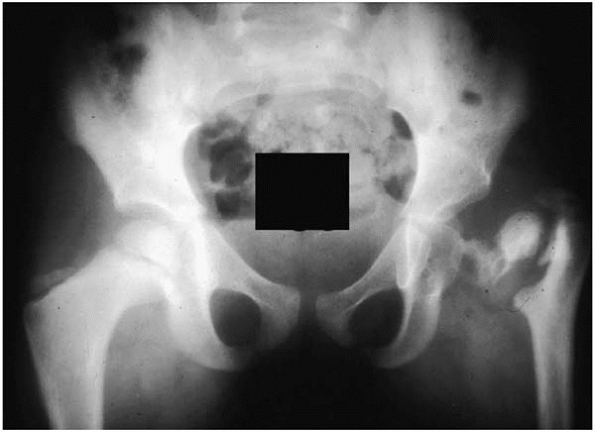

femoral neck? (See Fig. 16-5.) In this clinical scenario, it is best to get an MRI to determine why the child has not

had the expected clinical improvement. Finally, follow these children

for a couple of years afterwards to be certain that there is not AVN or

any proximal femoral growth disturbance (Fig. 16-6).

![]() |

|

▪ FIGURE 16-6 The disastrous consequences of missing a septic arthritis of the hip.